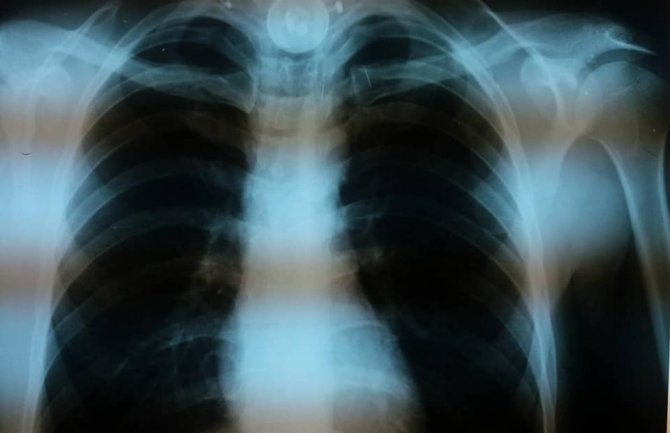

Doktor Kenan Erović specijalista anesteziolog i doktorka Branka Gogić specijalista ORL su prije dva dana izveli nesvakidašnji podvig i tako spasili život jednog Bjelopoljca.

Naime, u dramatičnoj situaciji su izvadili zadesno progutano strano tijelo iz jednjaka pacijenta, objavljeno je na Facebooku..

Procedura koju su izveli je zahtjevala vrhunsko znanje i prisebnost.